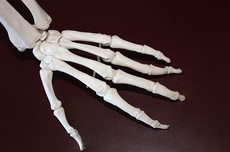

1. 강직: 아침에 일어났을 때 손가락, 손목, 발목 등의 작은 관절이 뻣뻣하고 움직이기 어려운 증상입니다. 이 증상은 30분 이상 지속되며, 피로감, 우울감, 식욕저하 등의 전신 증상과 함께 나타날 수 있습니다.

2. 관절 부종: 류마티스 관절염은 활막이라는 조직에 염증이 생기면서 관절 주위에 물이 차고 붓게 됩니다. 이로 인해 손가락이나 발가락의 마디가 부풀어 보이거나, 신발이나 반지가 잘 맞지 않는 경우가 있습니다.

3. 관절 통증: 류마티스 관절염은 주로 좌우 대칭적으로 작은 관절부터 통증이 시작됩니다. 통증은 압박감이나 쑤시는 느낌으로 나타나며, 활동을 하면 줄어들고, 쉬면 더 심해지는 경향이 있습니다.